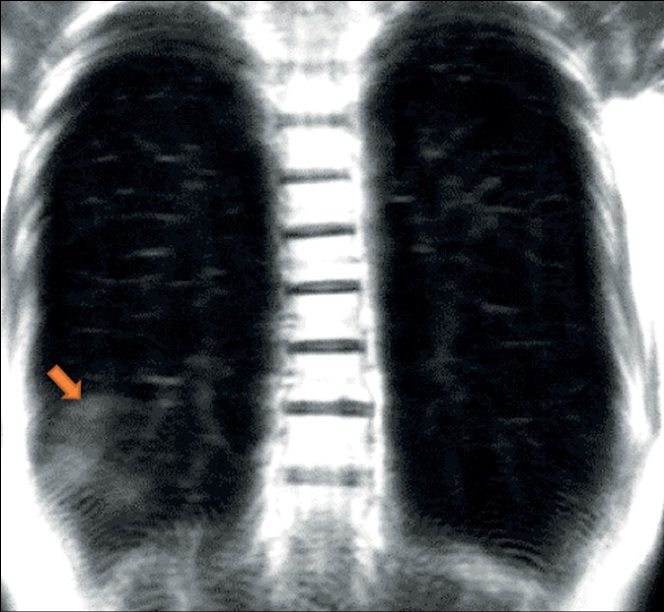

В представленной серии клинических случаев продемонстрированы возможности методики динамической магнитно-резонансной томографии в обнаружении признака «облачного неба» и его отличия от консолидации у пациентов с COVID-19, что позволяет предположительно разграничить раннее или лёгкое изменение от прогрессирующего клинического течения.

Таким образом, динамическая магнитно-резонансная томография может оказаться чрезвычайно полезным инструментом, к тому же без лучевой нагрузки, в случаях, когда доступ к компьютерной томографии ограничен и требуется динамическая морфофункциональная визуализация.